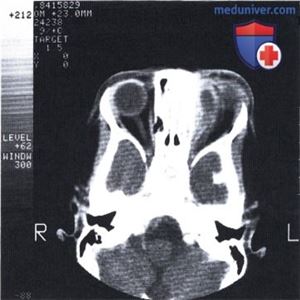

б) Визуализация:

• Инфильтрация поверхностных периорбитальных или глубоких внутриглазничных мягких тканей с контрастированием и развитием эффекта объемного образования

• В неосложненных случаях оптимальным методом исследования является КТ с КУ